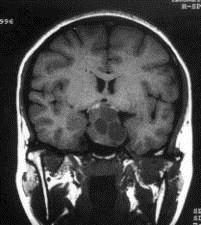

问题 病历摘要:??患者男性,35岁。性功能减退2年,视力下降6月。既往体健。体检:神清,皮肤细腻,毛发稀疏。视力左眼0.3,右眼0.5,双瞳等大等圆,直径3.5mm,对光反射稍迟钝,双颞侧偏盲,双眼底视神经乳头原发性萎缩,余神经系统未见异常。 关于鞍区周围的神经血管间隙的叙述哪些是正确的?